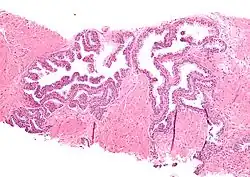

| Micrograph showing high-grade prostatic intraepithelial neoplasia. H&E stain. | |

High-grade prostatic intraepithelial neoplasia (HGPIN) is an abnormality of prostatic glands and believed to precede the development of prostate adenocarcinoma (the most common form of prostate cancer).[1][2]

It may be referred to simply as prostatic intraepithelial neoplasia (PIN). It is considered to be a pre-malignancy, or carcinoma in situ, of the prostatic glands.

HGPIN typically has one of four different histologic patterns:[2]

- tufted (fascicular patterning)

- micropapillary,

- cribriform and,

- flat.

Its cytologic features are that of prostatic adenocarcinoma:

- presence of nucleoli,

- increased nuclear-to-cytoplasmic ratio and,

- increased nuclear size.

Microscopically, PIN is a collection of irregular, atypical epithelial cells. The architecture of the glands and ducts remains normal. The epithelial cells proliferate and crowding results in a pseudo-multilayer appearance. They remain fully contained within a prostate acinus (the berry-shaped termination of a gland, where the secretion is produced) or duct. The latter can be demonstrated with special staining techniques (immunohistochemistry for cytokeratins) to identify the basal cells forming the supporting layer of the acinus. In prostate cancer, the abnormal cells spread beyond the boundaries of the acinus and form clusters without basal cells. In HGPIN, the basal cell layer is disrupted but present. PIN is primarily found in the peripheral zone of the prostate (75-80%), rarely in the transition zone (10-15%) and very rarely in the central zone (5%), a distribution that parallels the zonal distribution for prostate carcinoma.[7]